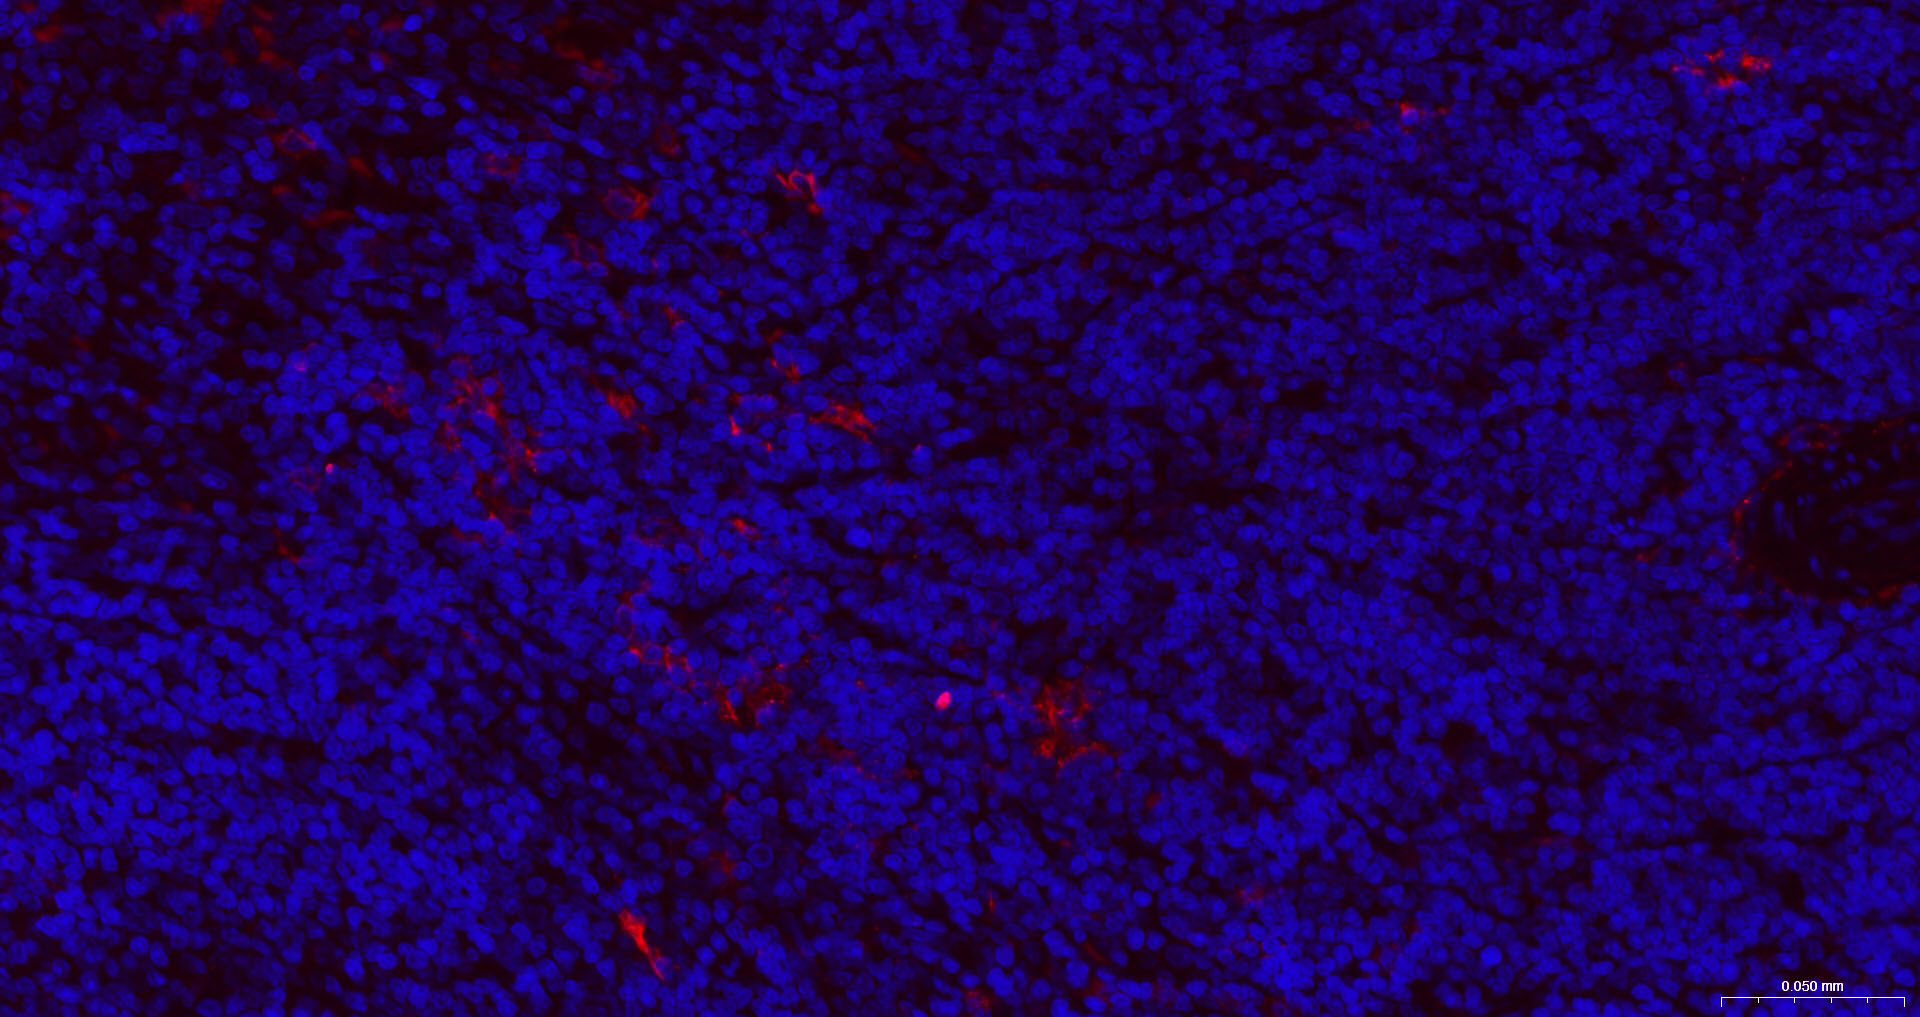

• IF(IHC-P)

IF(IHC-P) IFIHC-P1:100-500